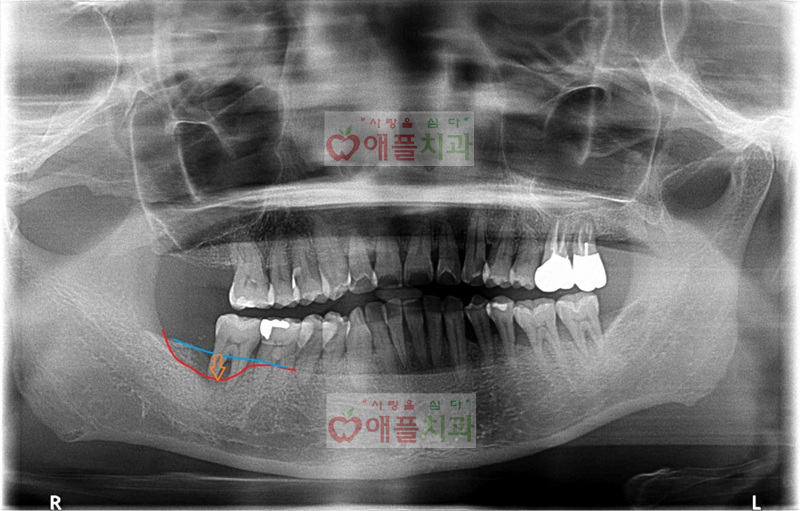

<처음 내원시>

하악 우측 어금니의 통증으로 내원하셨습니다. 치주염으로 인해서 골이 많이 소실된 상황이였습니다. 안타깝지만 발치를 해야하는 상황이며 발치후 골이식을 동반한 임플란트가 필요하다고 설명드렸습니다.

치주염으로 인한 치조골이 소실된 경우 치주치료로 치아를 계속 사용할수있는 경우, 그렇지 못하고 발치를 해야하는 경우가 있습니다.

애플치과는 3차원 치과용 정밀 CT를 통한 진단을 통해 결정을 합니다.

위의 환자분같은 상황은 발치를 해야하는 경우이며, 발치를 하면서 염증조직을 충분히 제거하고 케어하는것 또한 중요합니다.